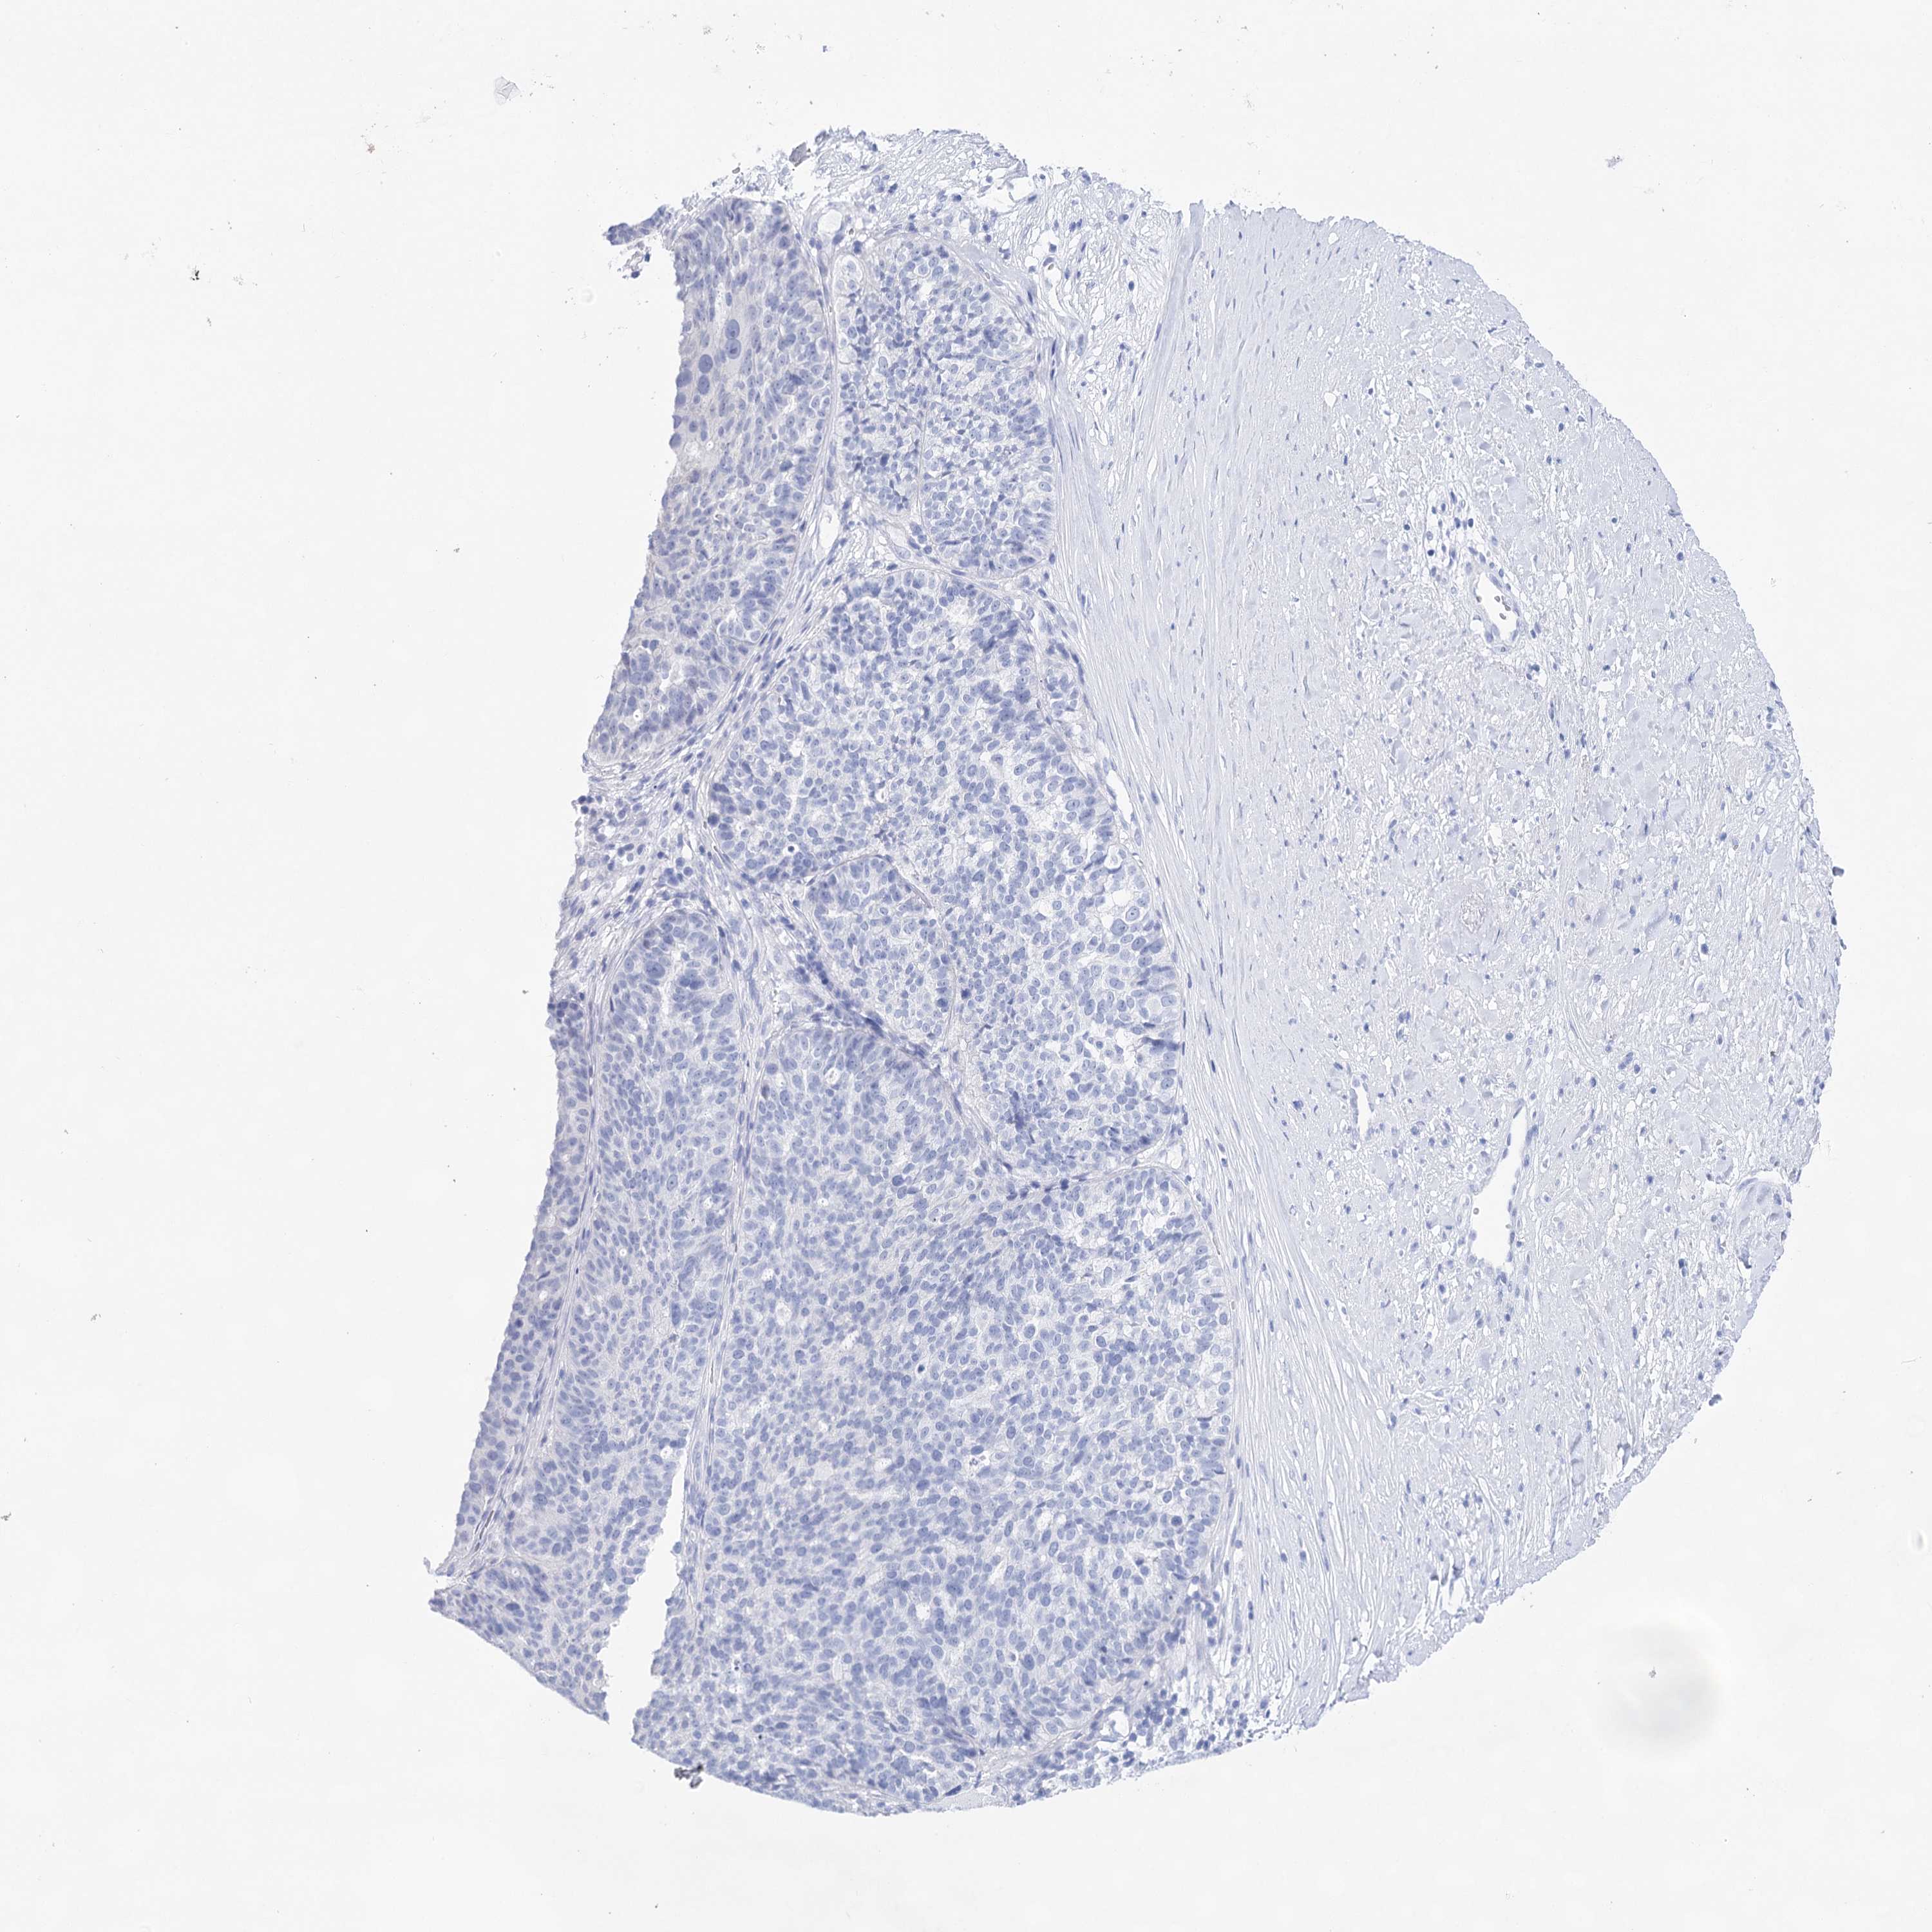

OVARIAN CANCER - Protein expressioni

A mouse-over function shows sample information and annotation data. Click on an image to view it in a full screen mode. Samples can be filtered based on level of antibody staining by selecting one or several of the following categories: high, medium, low and not detected. The assay and annotation is described here.

Note that samples used for immunohistochemistry by the Human Protein Atlas do not correspond to samples in the TCGA dataset.

Antibody stainingi

Antibody staining in the annotated cell types in the current human tissue is reported as not detected, low, medium, or high, based on conventional immunohistochemistry profiling in selected tissues. This score is based on the combination of the staining intensity and fraction of stained cells.

Each image is clickable and will lead to virtual microscopy that enables deeper exploration of all samples and also displays staining intensity scores, fraction scores and subcellular localization as well as patient and tissue information for each sample.

Antibody HPA029855

Antibody HPA029856

Antibody CAB026343

Cystadenocarcinoma, serous, NOS

Carcinoma, endometroid

Cystadenocarcinoma, mucinous, NOS

Carcinoma, NOS